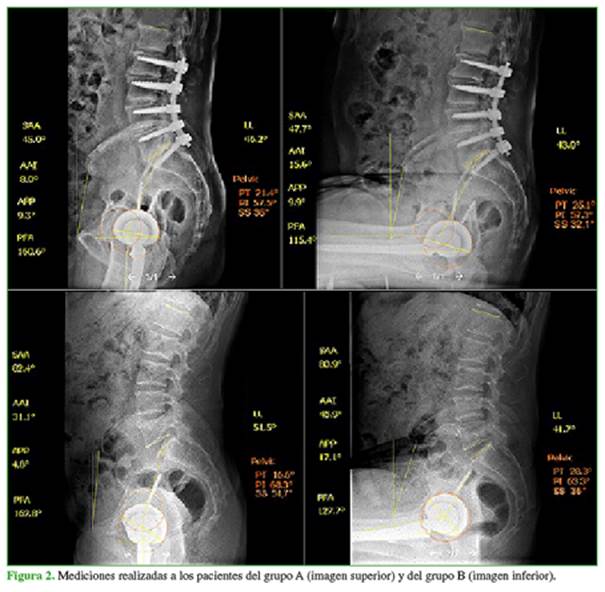

Se midieron los parámetros espino-pélvicos LL, PT, PI, SS, el plano pélvico anterior (anterior pelvic plane, APP), y los parámetros femoroacetabulares AAI, ángulo pélvico femoral (pelvic femoral angle, PFA). Las mediciones se realizaron en bipedestación y sedestación mediante el programa SurgiMap13 para Windows (Figuras 1 y 2).